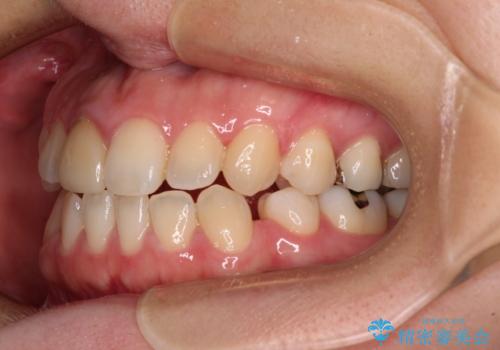

- 学生時代に行った抜歯矯正の後戻りで、隙間ができてしまったことを気にして来院された患者様です。

マウスピース矯正を検討されていましたが、後戻りの隙間が非常に大きく、奥歯を前方に移動させる必要があるため、ワイヤー装置にて矯正治療を行うこととしました。

舌の突出癖が非常に強く、その影響で隙間ができてしまったので、舌のトレーニングをしっかりと行っていただきました。

上顎歯列は歯の移動量が少なかったため、セラミッククラウンは装置を装着せずに治療を終えることができました。